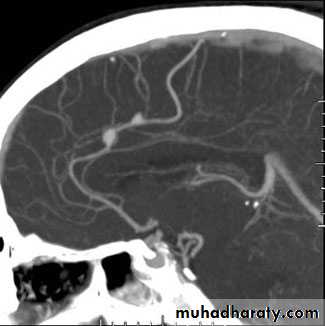

• CT and CT angiography

CT angiography: